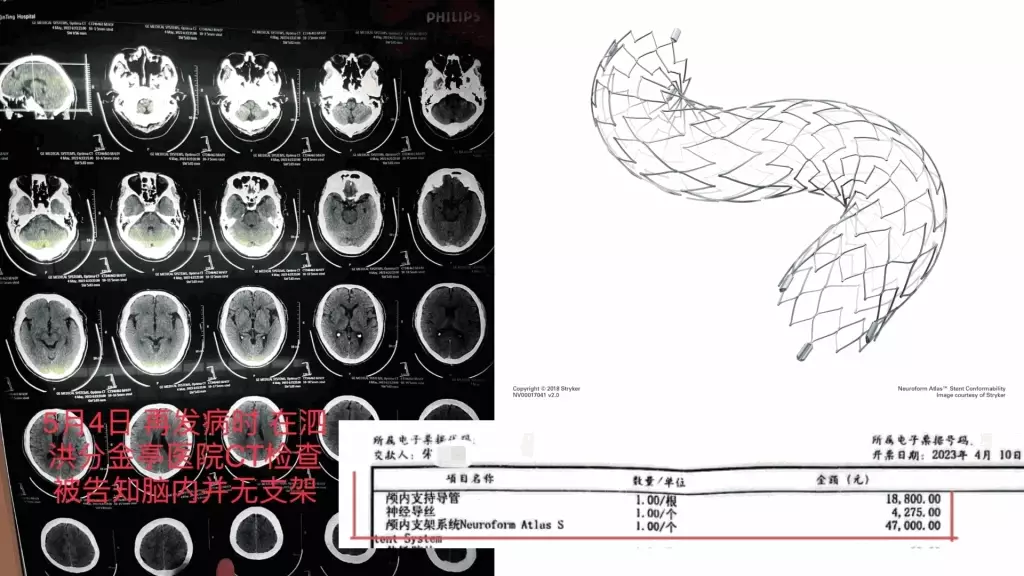

當時醫生告知家屬,如果不予血管內介入治療,患者隨時可能因動脈閉塞導致死亡。經家屬簽字同意,4月6日,齊某再次作為主刀醫生,對朱老翁進行經皮基底動脈支架植入術,術後告知家屬手術成功。手術記錄均顯示,朱老翁安裝了一枚進口Neuroform Atlas 4.5/21支架,病程記錄也多次提到「血管狹窄明顯改善」。朱老翁4月10日「康復」出院,家屬結清了住院醫療費用,合計12萬餘元,部分自費。收據顯示,其中顱內支持導管收費1.88萬,神經導絲4275元,而Neuroform Atlas進口顱內支架為4.7萬元。

到了5月4日,朱老翁突發嚴重腦梗,被救護車送至江蘇省宿遷市泗洪縣分金亭醫院搶救,CT檢查竟發現其顱內段部分動脈已嚴重堵閉,同時未有植入支架。朱先生無法接受,以為是小醫院檢查不出來,決定轉回宿遷市第一人民醫院,此時主刀醫生齊某才承認,之前植入支架失敗。

醫療費用明細顯示導管、支架等價值7萬元。

Neuroform Atlas 血管支架。 stryker官網